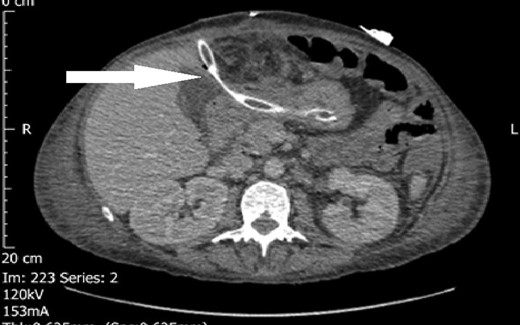

Following this second operation, the patient was discharged to intensive care unit (ITU); she initially did well and then was discharged to the ward. She failed to progress on the ward, developing a progressively worsening systemic inflammatory response, and a repeat computed tomography (CT) was undertaken (Day 13). This CT demonstrated a large loculated collection containing fluid and gas anterior to the left lobe of the liver that may be amenable to percutaneous drainage with free fluid throughout the abdomen with upper abdominal free gas. It also demonstrated diffuse fatty infiltration of the liver but no liver abscess. Diffuse fatty infiltration of the liver, but no liver abscess. Following this report, interventional radiological drainage was attempted but failed. Following this, her abdomen was found to be distended and tender with evidence of leak from gastric ulcer perforation.

The decision to take the patient back to theatre was made on Day 16 for an emergency laparotomy for attempted partial gastrectomy and formation of a controlled fistula. The wound was found to have broken down at the level of the fascia with bowel prolapsing out with pus and gastric contents leaking through with the large abscess collection in Left Upper Quadrant and contaminated gastric contents throughout the upper abdomen. The duodenum was unable to be mobilized due to dense peritoneal inflammation and contamination. It was decided to pass a transgastric drain through the abdominal wall and into the non-healing defect in the distal stomach to produce a controlled fistula. A further drain was placed external to the stomach to protect against a leak (Figs 1 and 2).